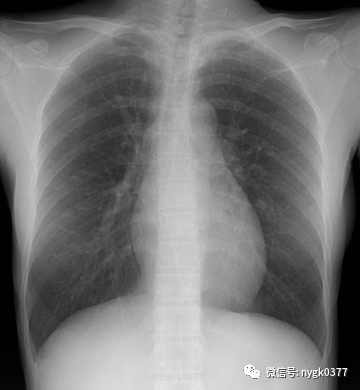

南阳市骨科医院新华路院区

近期我院引进日本岛津 C200多功能影像中心系统,该设备拥有性能完善的影像链系统,保证了其以很低的剂量得到优质的图像。配置的高性能动态平板探测器系统,使其图像质量更加优越。模块化设计理念使其功能更加丰富,覆盖了骨科、消化科、儿科、妇科、泌尿、等多科室应用。床体多中心运动设计,使其能更好的完成泌尿造影、ERCP、输卵管造影等应用需求。突破性的功能设计延伸到骨密度检查、金属关节置换周边图像采集、DSA等图像采集需要。

1、全胸片摄影(SID可拉伸到150CM)